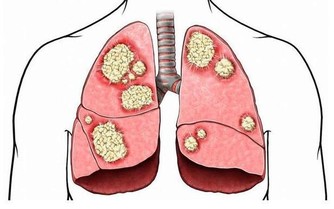

激躁性大腸症候群這個臨床上就有腹痛以及放屁等現象,如果是這個原因導致放屁增多的話,在飲食上就應該少吃多餐,千萬不能暴飲暴食。進食的時候一定要細嚼慢嚥,避免吃進去太多空氣了,同時呢上面我們講到的產氣的食物也要盡量避免不要吃,每天喝杯酸奶,有助於改變腸胃道的細菌。